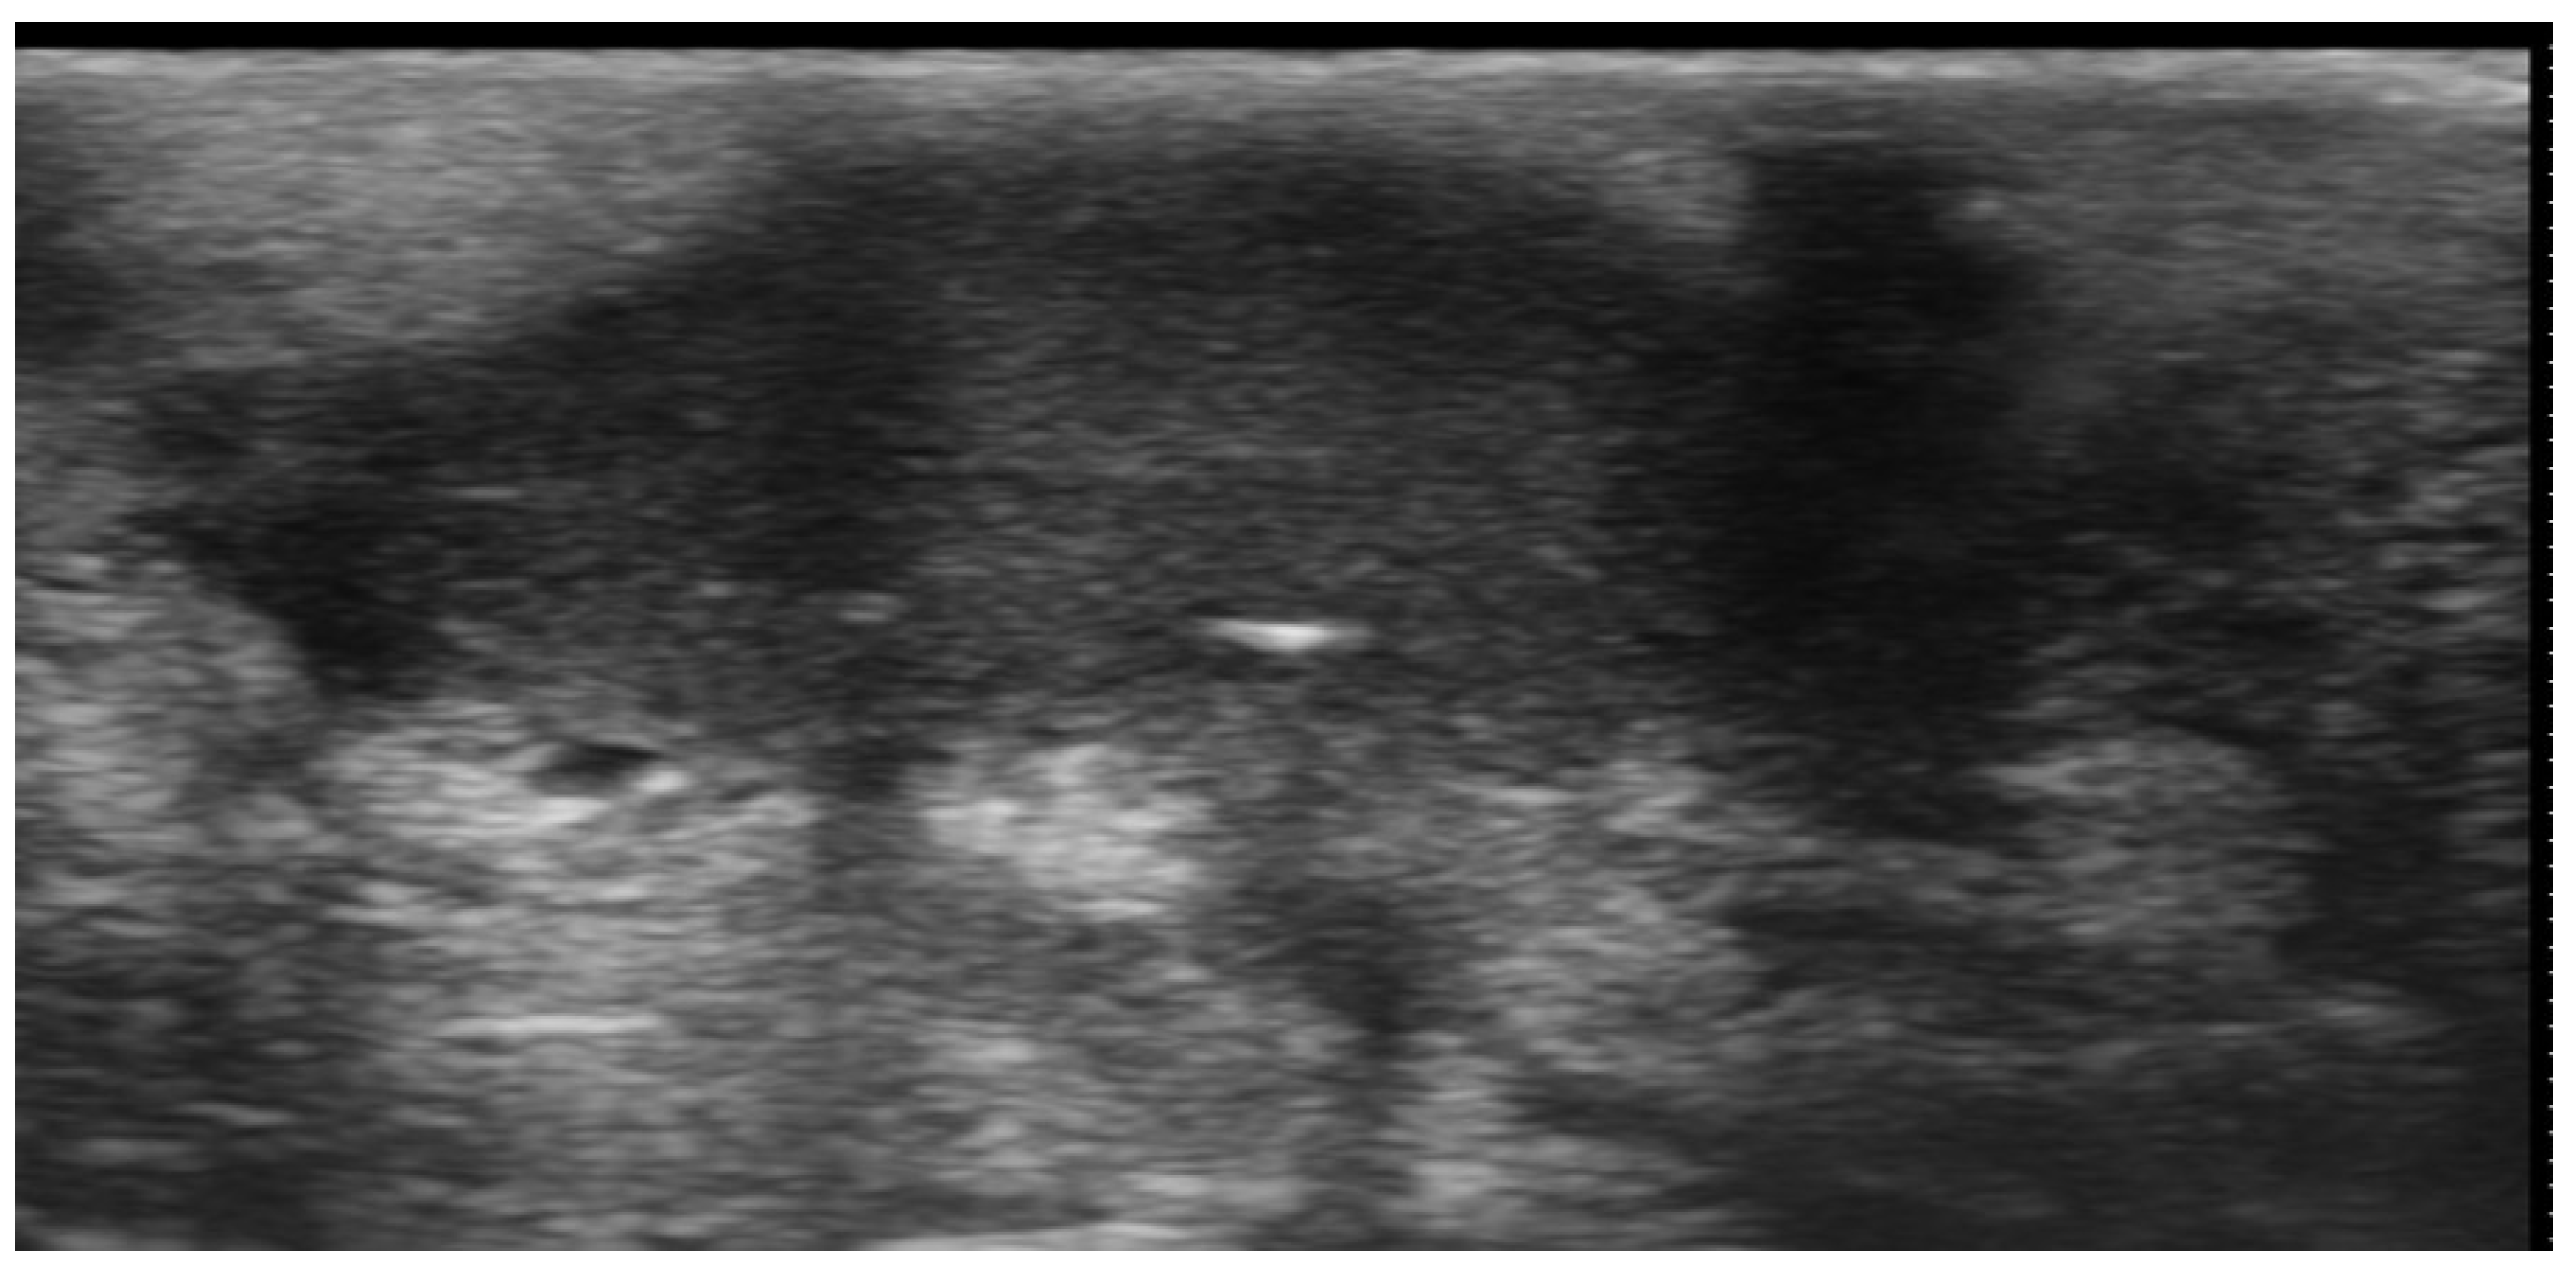

2. Infections